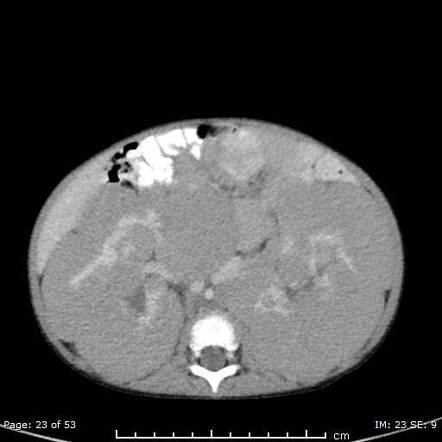

Nephroblastomatosis

multifocal/diffuse nephrogenic rests–> persistence of metanephric blastema

precursor to wilms

Associated with: BW, WAGR, and hemihypertrophy